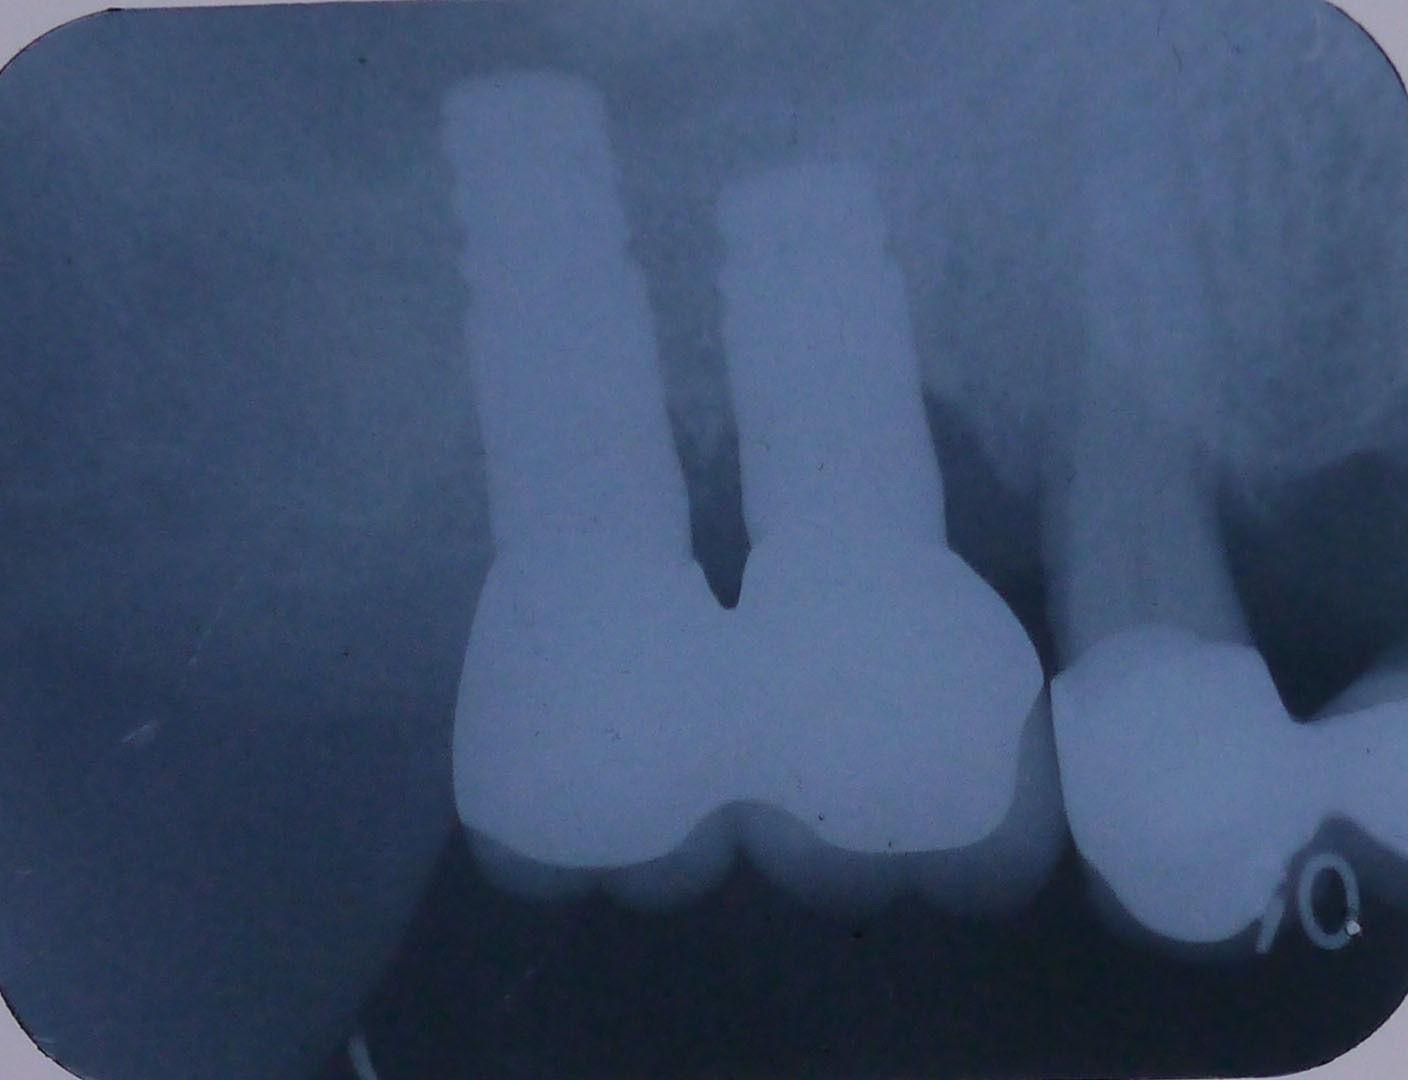

CT画像

上顎洞底の骨の厚さが右上7番で最低4mm、6番で2mm程度

埋入予定の骨を側面(頬側)から見たCT画像

平成24年9月 手術前のCT画像